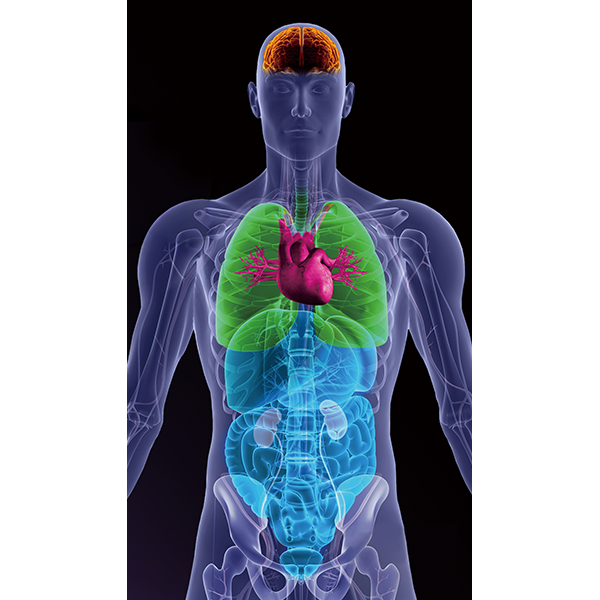

CT・MRIなどの断層画像から高精度な3D画像を描出し、解析を行う3D画像解析システム「SYNAPSE VINCENT Core」が、メディカルIT技術ブランド「REiLI(レイリ)」によるDeep Learningによって、さらなるバージョンアップを遂げました。膨大に蓄積された医用画像データを生かし、CTデータからの自動抽出機能や、脈管系の抽出機能が充実。画像認識技術を生かして、チーム医療を支え続けてきた富士フイルムだからこそ実現できた、AI時代の3D解析技術です。富士フイルムの「REiLI」が、チーム医療の最前線へと導きます。

「REiLI」によるDeep Learningを用いた臓器抽出で画像処理を簡単に行うことが可能です。